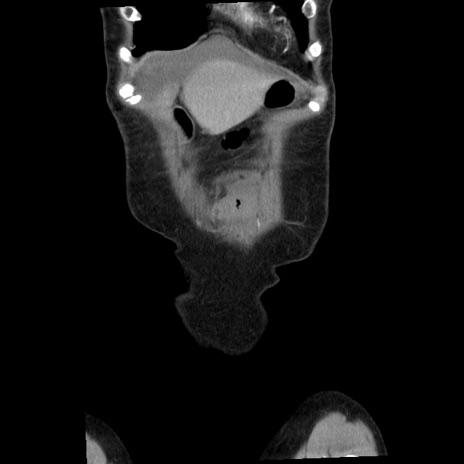

矢状断像

【症例】80歳代女性

【主訴】腹痛

【現病歴】8時間前から腹痛あり来院。

【既往歴】糖尿病、脂質異常症、子宮体癌にて子宮全摘術

【身体所見】意識清明・会話良好だが腹痛で苦悶様、全腹部にわたって反跳痛と圧痛あり

【データ】WBC 13600、CRP 0.14、LDH 224、CK 90